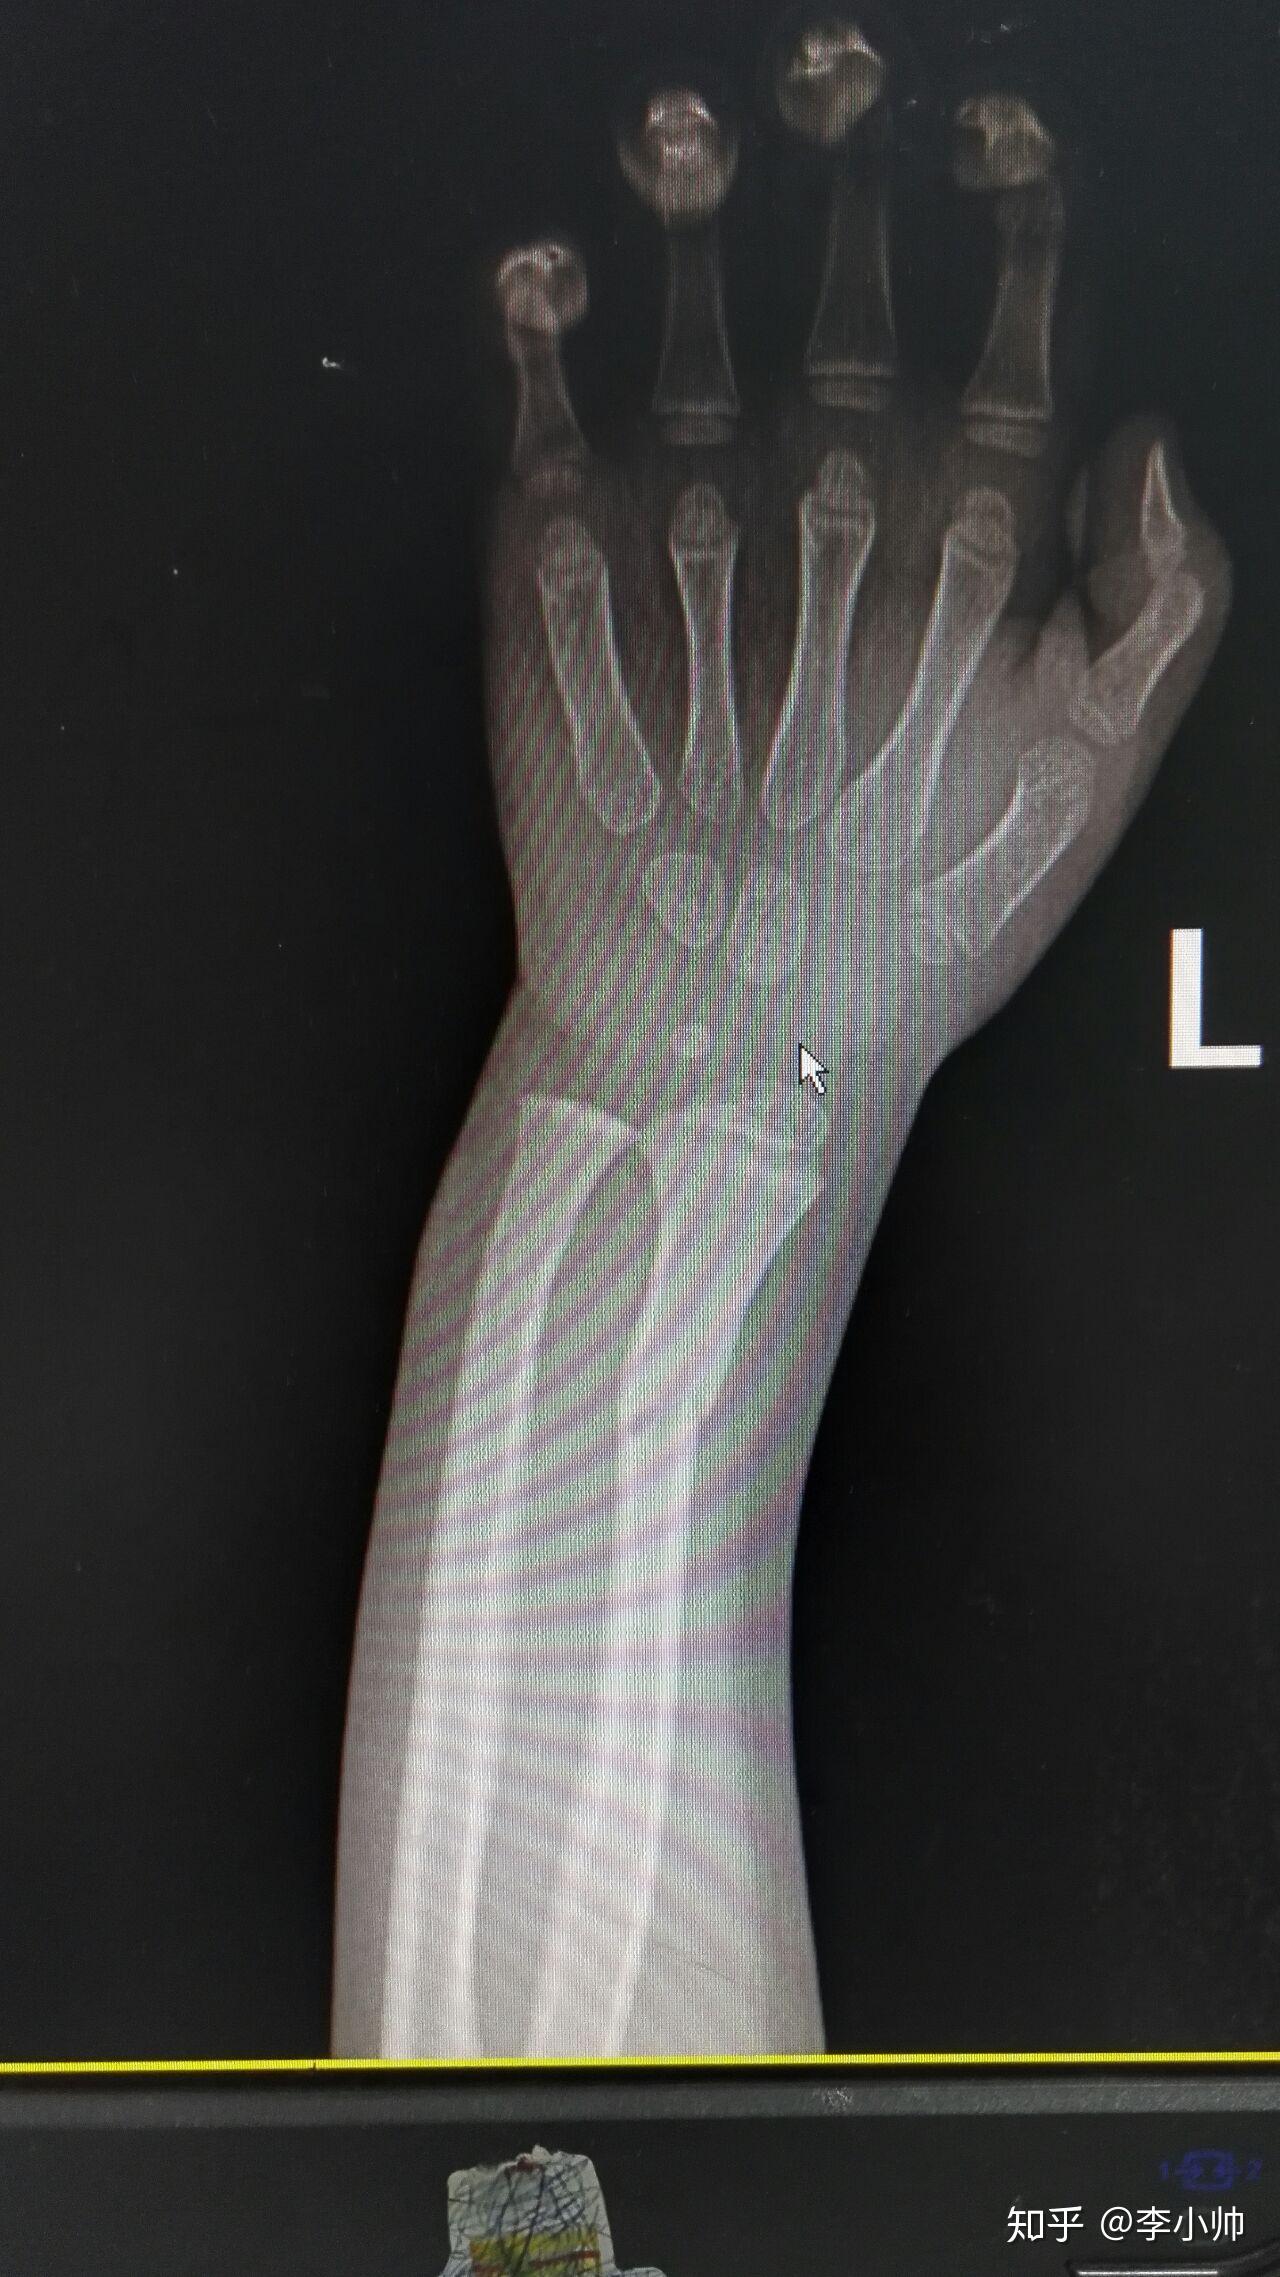

14岁胫腓骨远端骨折闭合复位外固定架固定手术一例

图片尺寸1948x3284